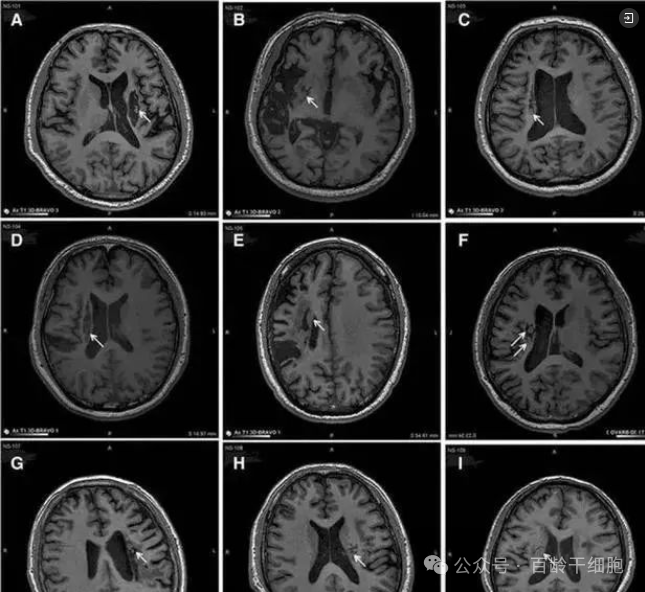

2019年,我国某医院在《干细胞转化医学》杂志上公布了一项令人振奋的研究成果。他们发现,干细胞回输有助于脑卒中偏瘫患者运动功能的恢复。在这项临床研究中,9名年龄在30至65岁之间的偏瘫患者接受了干细胞的脑内回输。这些患者在中风后5-24个月接受了治疗,干细胞被精确地回输至脑内梗塞灶附近。

影像学研究的结果令人振奋,干细胞输入区出现了新的神经组织,这证明了干细胞干预偏瘫性脑卒中具有一定的临床益处。通过24个月的随访,临床结果显示,相对于基线,患者的分数发生了显著变化,9例患者的影像学显示病变区域的组织都发生了明显变化。

图片

这项研究的成功在于,回输到脑内梗塞病灶的干细胞能够分化为神经系统的各类细胞,并分泌营养因子。这些因子促进了神经和血管的再生,修复了受损的血-脑脊液屏障,并减轻了炎性反应。这一系列的作用共同促进了脑梗死动物的神经功能恢复,使得9例临床患者的偏瘫症状得到了明显改善。